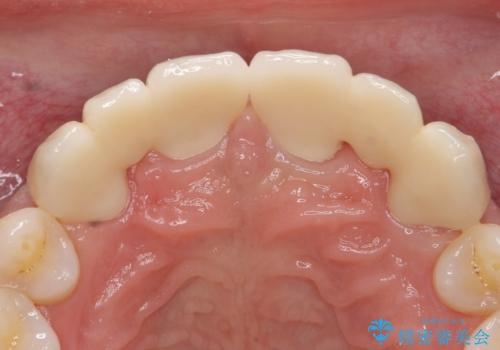

- 前歯部のすきっぱと歯並びが気になるので診て欲しいといらっしゃった方の症例です。

全顎矯正は御希望されなかったため、上顎前歯部のみの部分矯正とオールセラミッククラウンによる補綴を行いました。

今回用いたオールセラミッククラウンはジルコニアフレームという白い素材の上にセラミックを盛っているため、審美性が非常に高いのが特徴です。

また、ジルコニアは人工ダイヤモンドの材料にも使われているほど高い強度を持っており、そのためオールセラミッククラウンは審美性だけでなく、奥歯やブリッジの補綴も可能とするクラウンです。